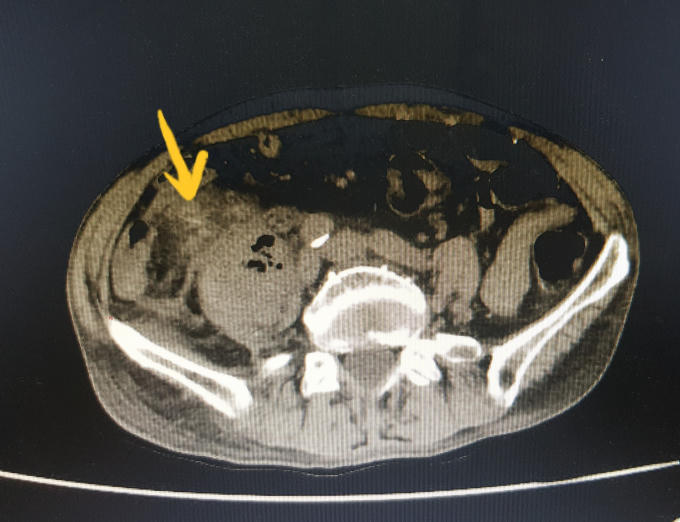

Vị trí nơi chiếc tăm đâm thủng ruột cụ ông 72 tuổi.

Sau khi thăm khám và chụp cắt lớp ổ bụng bệnh nhân, các bác sĩ phát hiện hình ảnh nghi dị vật (tăm) dài khoảng 5 cm xuyên thủng ruột vị trí hồi manh tràng, đâm vào cơ thắt lưng chậu phải gây áp xe và phản ứng viêm vùng hố chậu phải.